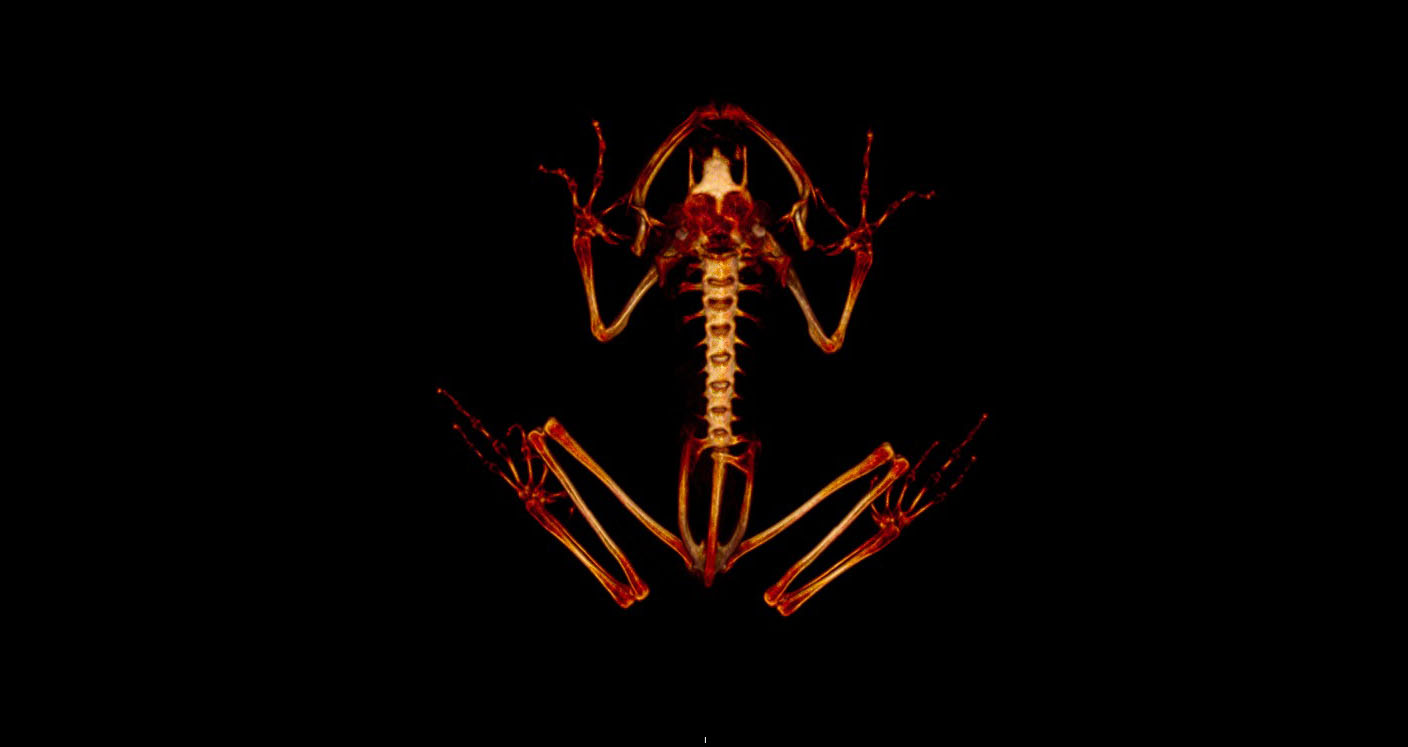

Helping Frogs Grow Stronger Bones

Lemur frogs awaiting their micro-CT scan

Maria Graciela Aguilar, who recently successfully defended her PhD thesis at the LSU School of Veterinary Medicine, is from Costa Rica and a lover of the lemur tree frog, a critically endangered species.

To help conserve these beautifully green amphibians, conservationists may need to maintain these frogs in protected environments in captivity. But to do so, they also need to know how to properly feed these frogs and maintain them for optimal health and reproduction.

Aguilar has been studying how much food these frogs typically eat in a day and how to ensure they get enough calcium to keep their bones strong. In a recently published study, Aguilar and colleagues used micro-CT scans of live frogs to assess bone density and whether adding extra calcium to the insects the frogs ate could improve it.

The results were promising: the frogs on the higher calcium diet had higher bone density.

“We also found that how you determine bone density was very important, something that other studies should consider in the future,” said Mark Mitchell, professor of zoological medicine at LSU VetMed and senior author on the new study.

“Most studies only take a section of bone for the image, but Graciela ended up using the whole skeleton because these frogs are so tiny. This also helps prevent errors that occur when you only select one bone that may be remodeling at a different rate than other bones.”

The study helped Aguilar and colleagues determine how best to prepare foods for these critically endangered frogs in captivity, how to most accurately measure bone density over time, and how to successfully anesthetize the frogs for scanning without harming them.

Lemur frog CT scan.